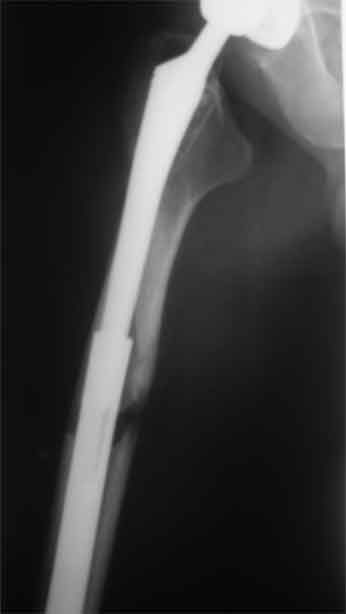

Произведено закрытое удлинение ножки эндопротеза с помощью ретроградного интрамедуллярного стержня. Продолжительность операции 3 часа. Два из них закрытое восстановление длины бедра диистрактором

таз-бедро.

А нельзя ли увидеть и профиль бедра на всем протяжении, т.е. и весь протез, и весь стержень? И фас бы с коленом.

новые снимки